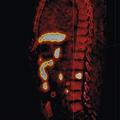

Dans certaines circonstances particulières (progression rapide du PSA), une SA androgénique peut être indiquée. Elle conduit parfois à une résistance à la castration, justifiant la prescription d’HTNG. Dans ce contexte, on réalise régulièrement une tomographie par émission de positons (TEP ; figure ) marquée à la fluorocholine, qui localise dans plus de 80 % des cas le site de la récidive et permet un traitement adapté à celle-ci.